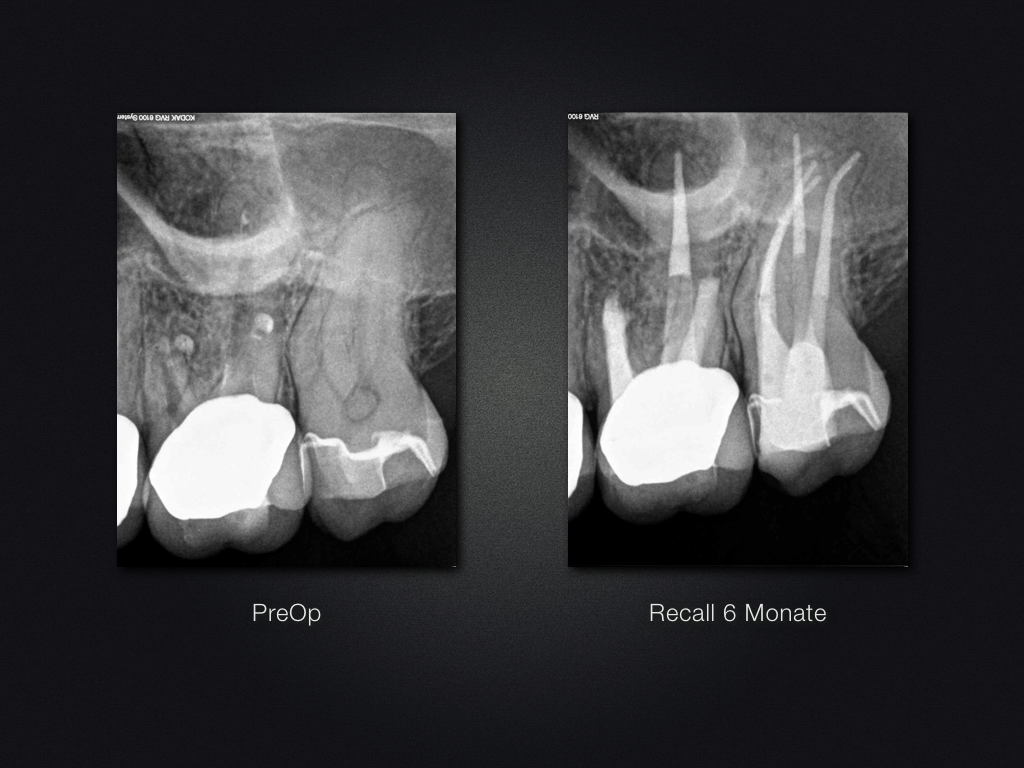

26D.010

2D vs. 3D (XXVI)